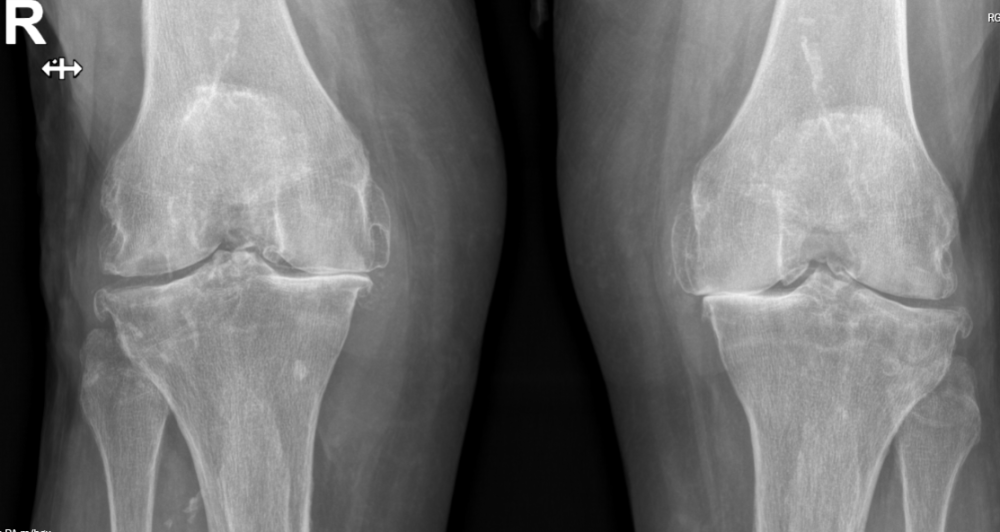

Gjennomgang av RTG-og MR-bilder.

Ortopedi

Her kan du få en grundig vurdering hos en erfaren ortoped med kort ventetid.